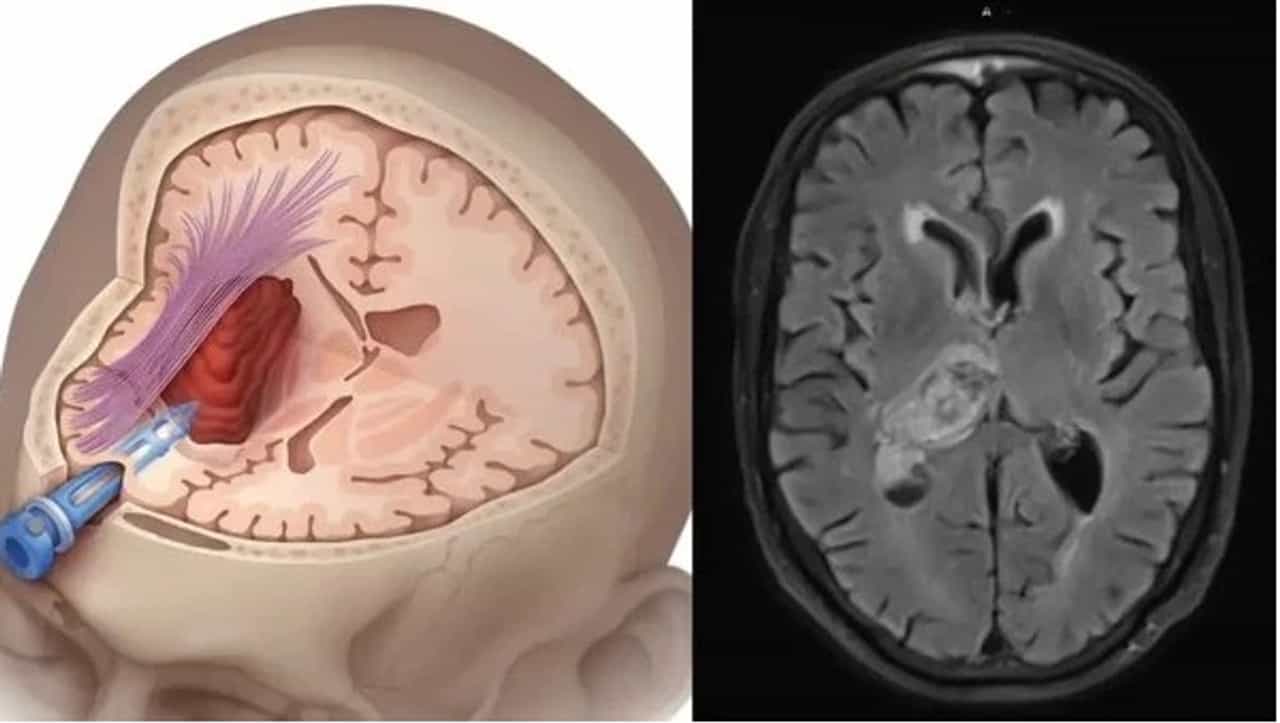

मेंदूच्या नसांमध्ये रक्तप्रवाह करणाऱ्या नसांना दुखापत झाली किंवा त्या फुटल्या तर आपल्याला पक्षाघात किंवा ब्रेन स्ट्रोक येत असतो. त्यामुळे शरीराचे अवयव लुळे होऊ शकतात. किंवा दृष्टी, बोलणे वा चालणे अथवा ऐकणे अशा क्रियांवर परिणाम होऊन त्या बंद देखील पडू शकतात. किंवा मेंदूत अधिक रक्तस्राव झाला तर मृत्यू देखील येऊ शकतो..

जेव्हा मेंदूची एखादी नस ब्लॉक होते तेव्हा ब्रेन स्ट्रोक येतो. या जीवघेण्या स्थिती वेळीच उपचार न केल्यास मृत्यू देखील येऊ शकतो.परंतू तुम्हाला मिनी ब्रेन स्ट्रोक बद्दल माहिती आहे का? जो एखाद्या मोठ्या अटॅक येण्याआधीच येऊ शकतो.याची लक्षणं हलकी असतात. त्यांना वेळीच ओळखले तर मोठा अटॅक येण्यापासून वाचता येते. याला मिनी ब्रेन स्ट्रोक वा ट्रान्सिएंट इस्केमिक अटॅक देखील म्हणतात

ब्रेन स्ट्रोक सारखा छोटा ब्रेन अटॅक देखील मेंदूची एखादी नस ब्लॉक झाल्याने येऊ शकतो. NHS (ref.) च्या नुसार याचे कारण मेंदूला ऑक्सीजन मिळणे बंद होते. परंतू हे नुकसान स्थायी नसते. आणि २४ तासात आपोआप बरे देखील होत असते. परंतू याच्या लक्षणांना गंभीरतेने घ्यायला हवे आणि डॉक्टरांचा सल्ला तातडीने घेणे गरजेचे असते.